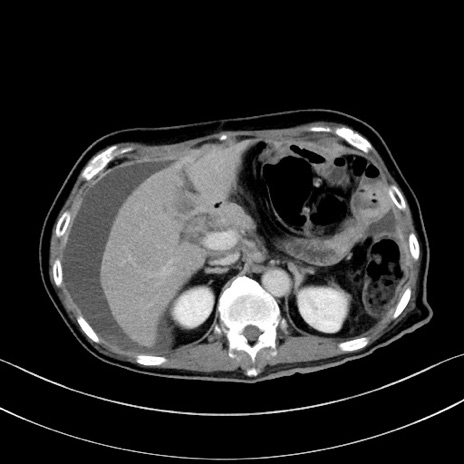

冠状断像

【症例】60歳代男性

【主訴】嘔吐

【現病歴】胃癌にて胃全摘後。食思不振が悪化し、夜中に嘔吐することがある。

【既往歴】胃癌、胃全摘、脾摘、胆摘後

【データ】WBC 5900、CRP 10.56